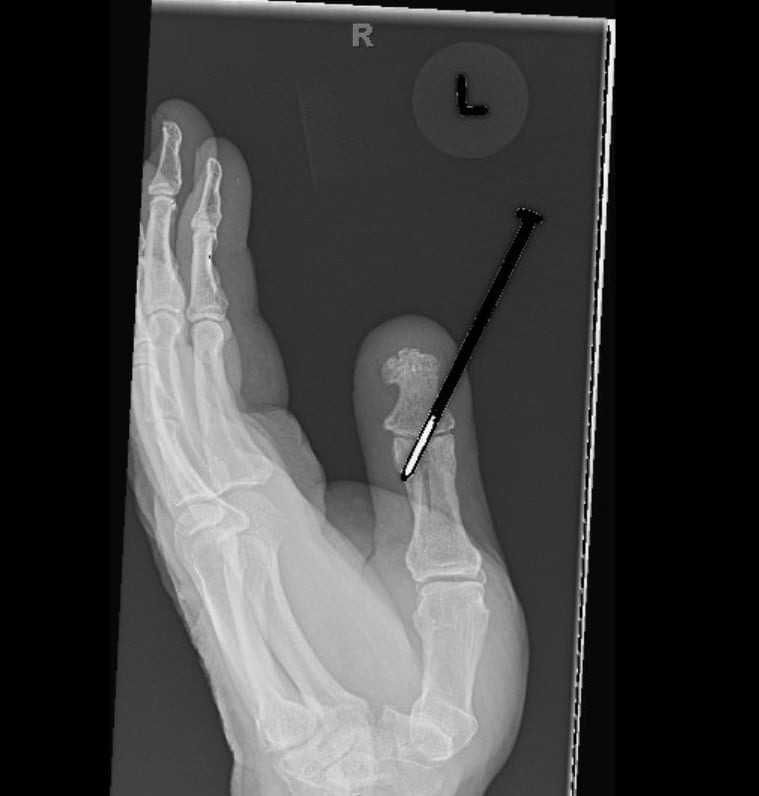

Radiographs were obtained including anterior-posterior and lateral views of the left thumb which demonstrated a penetrating injury of a metallic object (in this case, the threaded nail). The nail on X-ray did appear to pierce the base of the distal phalanx with extension through the interphalangeal joint into the thumb proximal phalanx with an associated vertically oriented split fracture of the proximal phalanx, evident with increased radiolucency on these films. No gas within the soft tissues or other identified foreign bodies; fractures, dislocation, or other acute bony abnormalities were noted. The hospital site has an orthopedic surgery residency program, and the orthopedic surgery resident was consulted given the bony involvement and the recommended outpatient management with an orthopedic hand surgeon.

Post-foreign body removal with cast application X-rays were obtained which redemonstrated the vertically oriented, longitudinal fracture of the left thumb proximal phalanx extending into the interphalangeal joint. Removal of the foreign metal nail also allowed for appreciation of an intra-articular fracture at the distal ulnar aspect of the proximal phalanx where the metallic nail had been previously located, and a distal phalanx base fracture as well. No retained metallic foreign bodies were identified. Of note, there was no involvement of the metacarpal phalangeal joint of the thumb, making this an isolated injury involving only a single joint of the thumb.